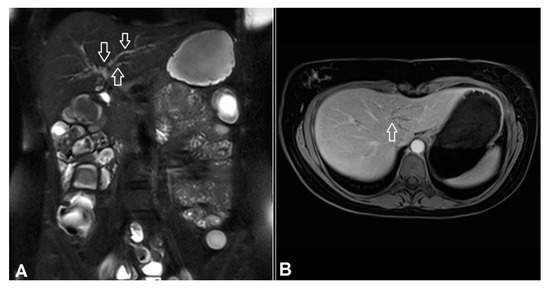

3.6. Extra-Intestinal Findings